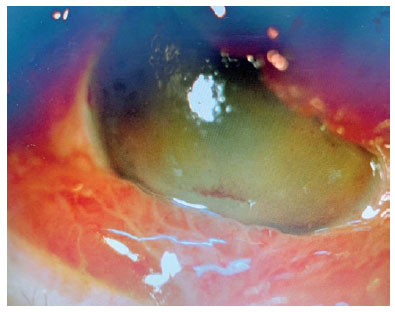

The patient received contrast tomography of the orbit, which revealed dilatation of the superior ophthalmic vein, while arteriography revealing a ruptured saccular aneurysm in the intracavernous portion of the right internal carotid that induced an arteriovenous fistula of the CS (Figure 3A-B). Together with the Neurology and Interventionist Radiology team, it was decided to perform endovascular closure of the fistula (Figure 3C). Anomalous communication was successfully treated (Figure 3D-E), which reduced the eyelid edema and chemosis (Figure 4). Even with treatment, however, corneal edema, hyphema, and vitreous hemorrhage were (4+/4+) on ocular ultrasound, and RE UCVA decreased to near complete absence of light perception. At a 3-month follow-up examination, there was partial improvement of corneal edema and hyphema but no improvement in VA.

11-fig04.jpg)

We have found no previous reports on corneal edema, hematic impregnation, or hyphema secondary to CCF as observed in this case. It is possible that these findings may be associated with the severity of fistula (e.g., IOP)(11,12). When present, these signs may help in the differential diagnosis between orbital cellulitis and CCF(12).